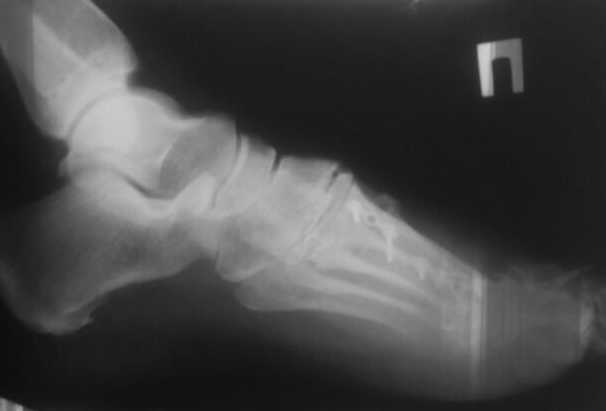

женщина средних лет, оперирована около года назад

Насколько я понял, беспокоит метатарсалгия. Достаточно будет укоротить

II-IV? Что-то другое? на что обратить внимание?